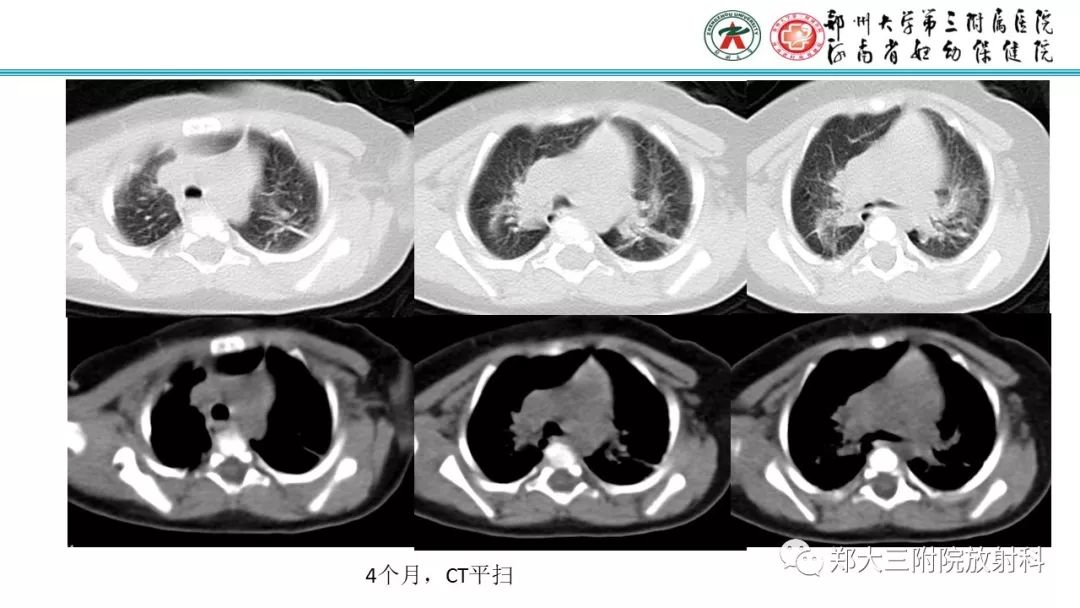

DiGeorge迪格奥尔格综合征1例CT